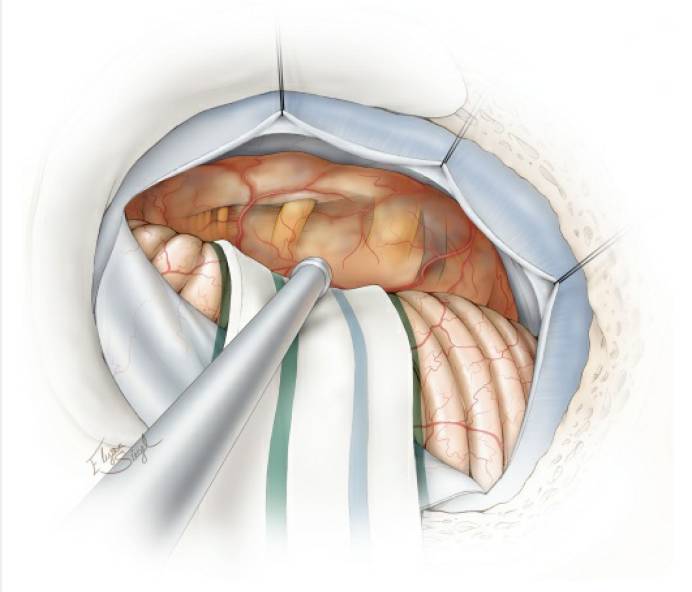

图8. 下一步,使用超声吸引器对肿瘤进行瘤内减压。血供已断的肿瘤减压效率更高,因为此时不需要在瘤腔内重复“切除-止血”的步骤。注意,肿瘤前面的包膜需完整保留,勿大意损伤。

图9. 充分的瘤内减压使得肿瘤包膜移动灵活,从而无需对正常组织结构进行不必要的牵拉。然后将肿瘤下极包膜与后组颅神经进行锐性分离。注意仔细保留包绕神经的蛛网膜,细致松解粘连的血管。

图10. 接下来,肿瘤上极可与天幕和三叉神经分离。此时,岩上静脉已被牺牲,笔者继续寻找滑车神经(被增厚的蛛网膜层包绕)并避免对它直接操作,以保护其功能。注意保留小脑上动脉发出的过路动脉。